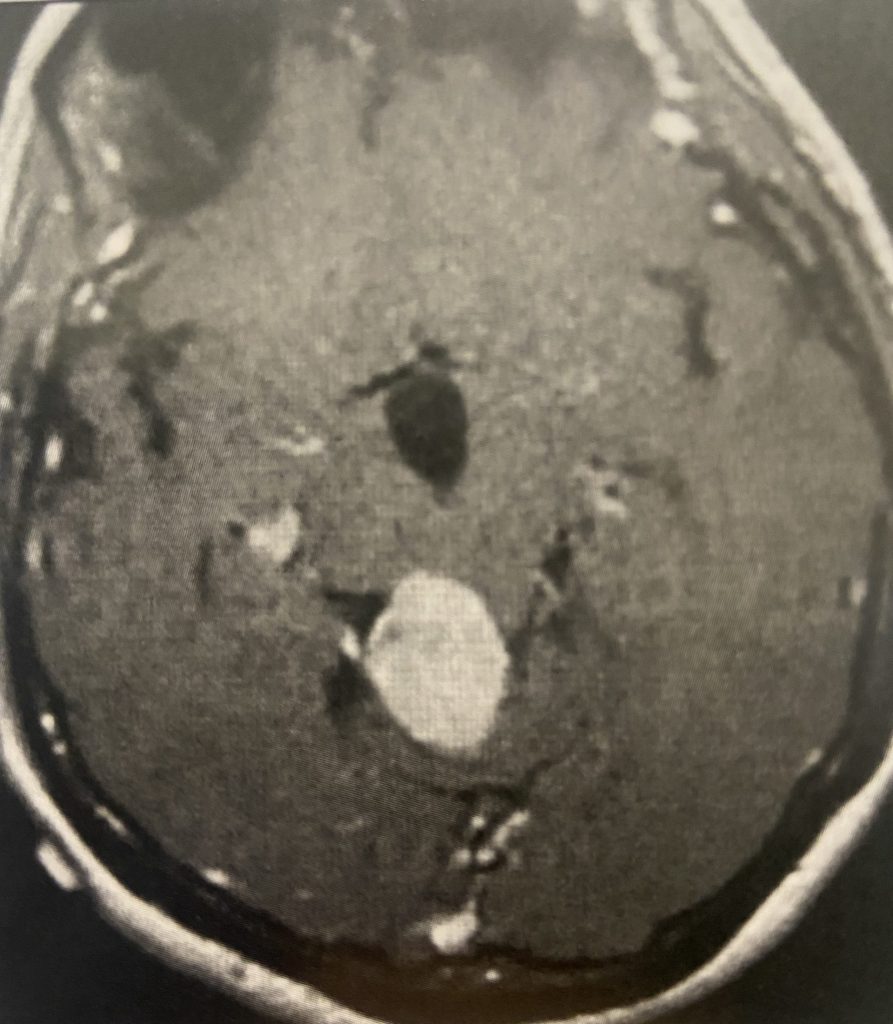

This is a 57-year-old woman with new onset memory problems and gait difficulty. MRI demonstrated a 3 cm tumor in the pineal region, most consistent with a meningioma growing inferiorly off the right tentorium.

Figure 1: Preop post contrast axial MRIs demonstrating a pineal region meningioma with hydrocephalus.

The tumor was causing compression of the upper brainstem and hydrocephalus. The tumor was removed by Dr. Michael Brisman using a right occipital / transtentorial approach.

This tumor seemed most likely to be a meningioma, given its regular shape, homogeneous enhancement pattern, and attachment to the tentorium.